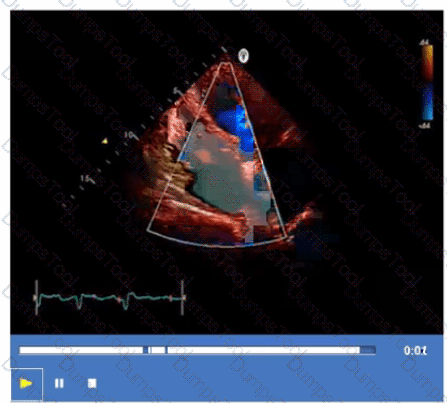

Which coronary artery territory is associated with the wall motion abnormality demonstrated in this video?